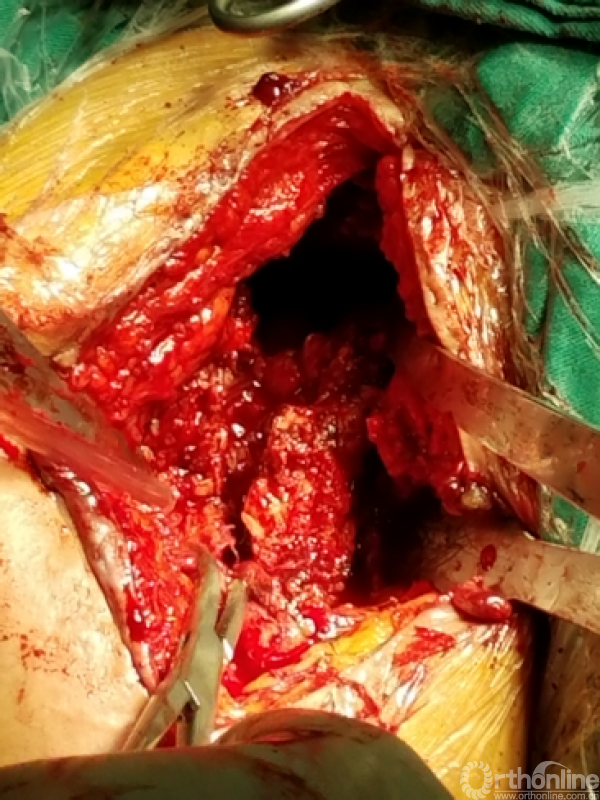

关节盂正常结构消失,至喙突偏内侧部位,上方紧贴肩峰下,仍然有骨质可用!

咬除连接骨桥,清理髓腔,恢复活动度

安尔碘溶液反复冲洗1000毫升,浸泡!!!

1.关节盂正常结构消失,前倾增大。

2.紧贴喙突内侧

3.骨质菲薄

4.特别小心肌皮神经及腋鞘

骨质疏松明显,皮质成虫蚀样改变,外侧缺损。

1.抗生素骨水泥占位器植入

2.不锈钢克氏针+抗生素骨水泥

3.柄部没有骨水泥,利于引流,头部较原有假体头部偏大,减少挛缩,占位关节腔,颈干角及后倾维持

4.用肌腱缝线固定减少排斥

5.后内侧结构尽量不去干扰,防止出现神经血管损伤。